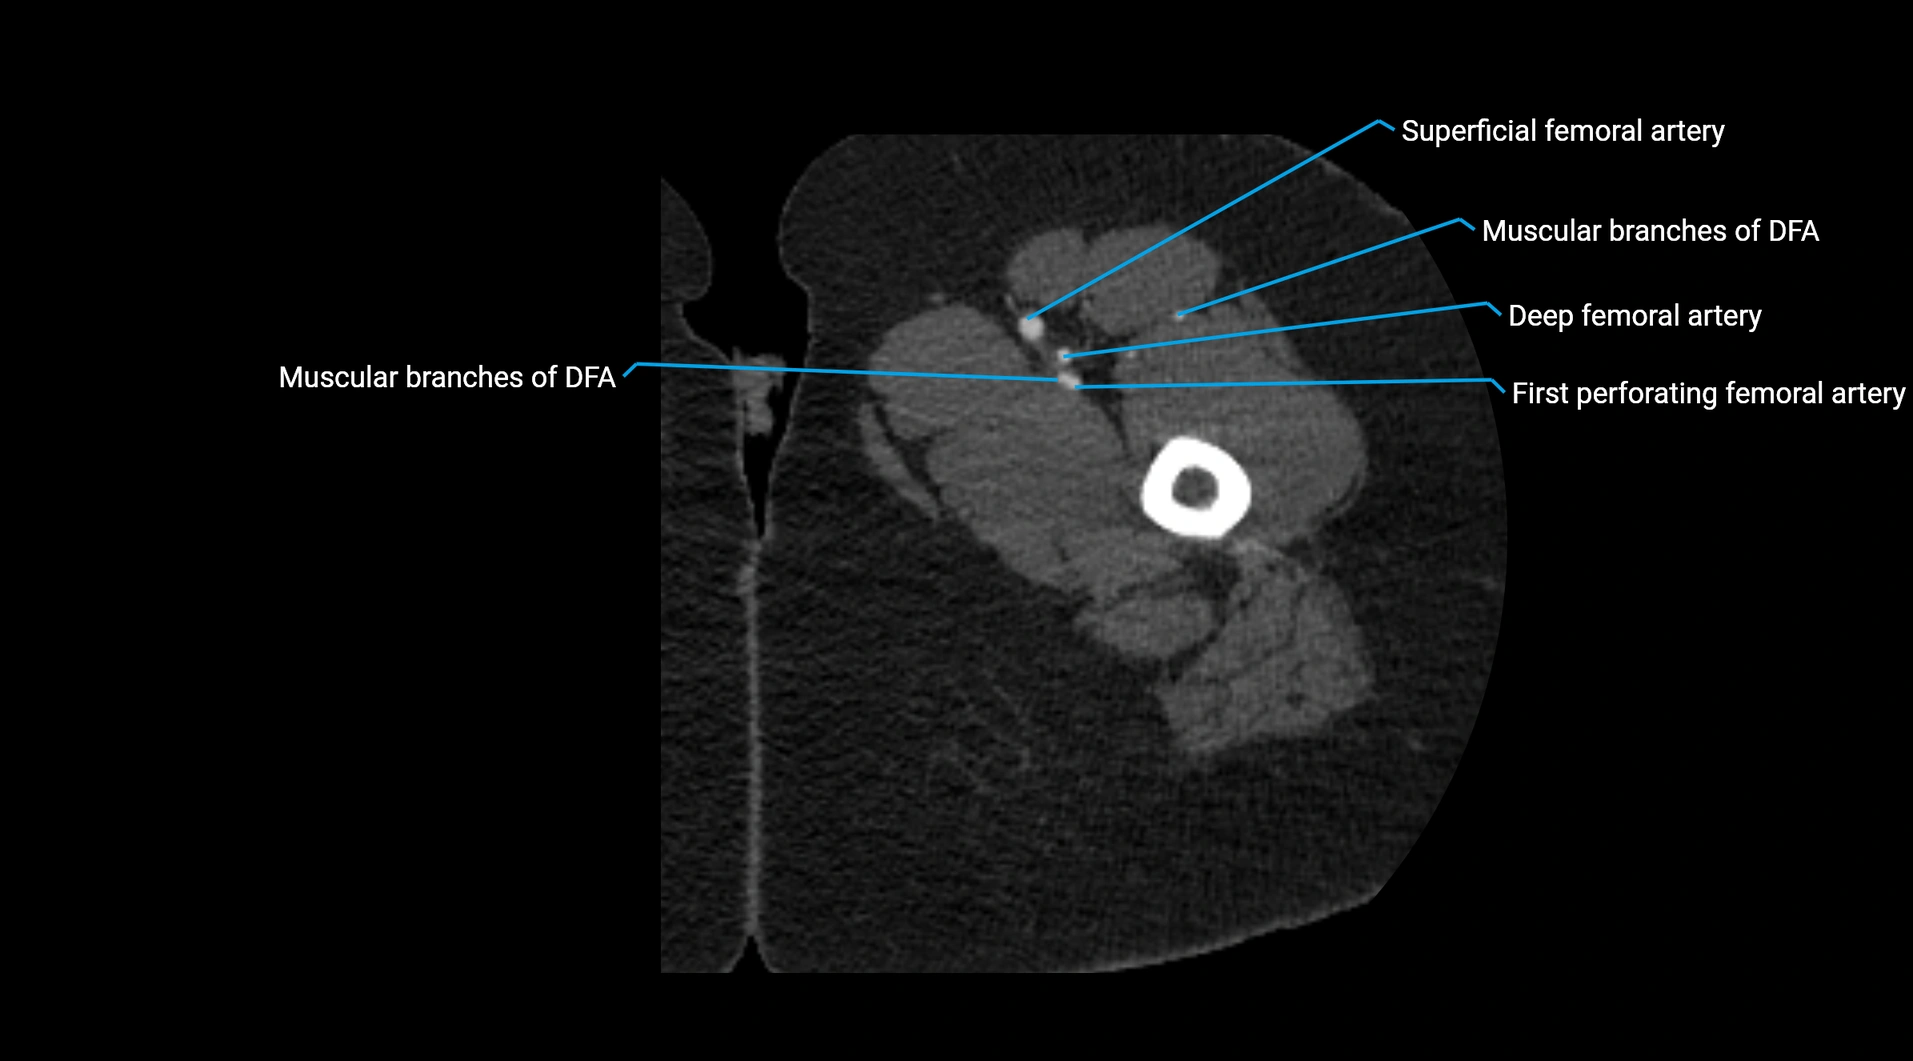

CT images

image

Contrast-enhanced CT (CTA):

• Gold standard for abdominal aortic imaging

• Provides excellent detail of lumen, wall, aneurysm, thrombus, and branch vessels

• Multiplanar and 3D reconstructions help in aneurysm measurement, stent graft planning, and dissection evaluation

• Detects acute rupture, traumatic injury, or occlusion with high sensitivity